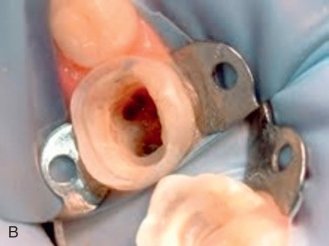

Removing the Infection

• Gently removing the infected or damaged pulp tissue.

• Cleaning and disinfecting the inside of the tooth.

Sealing the Tooth

• Filling the tooth with a biocompatible material to prevent reinfection.

• Placing a temporary or permanent crown for added protection.